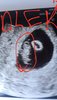

Zobaczcie jaki jestem piękny

Skierowanie na bete mi dała gin wczoraj

Mój bąbelek ma 13mm i serduszko 147 uderzeń na minutę, Pan doktor powiedział że pięknie to wygląda